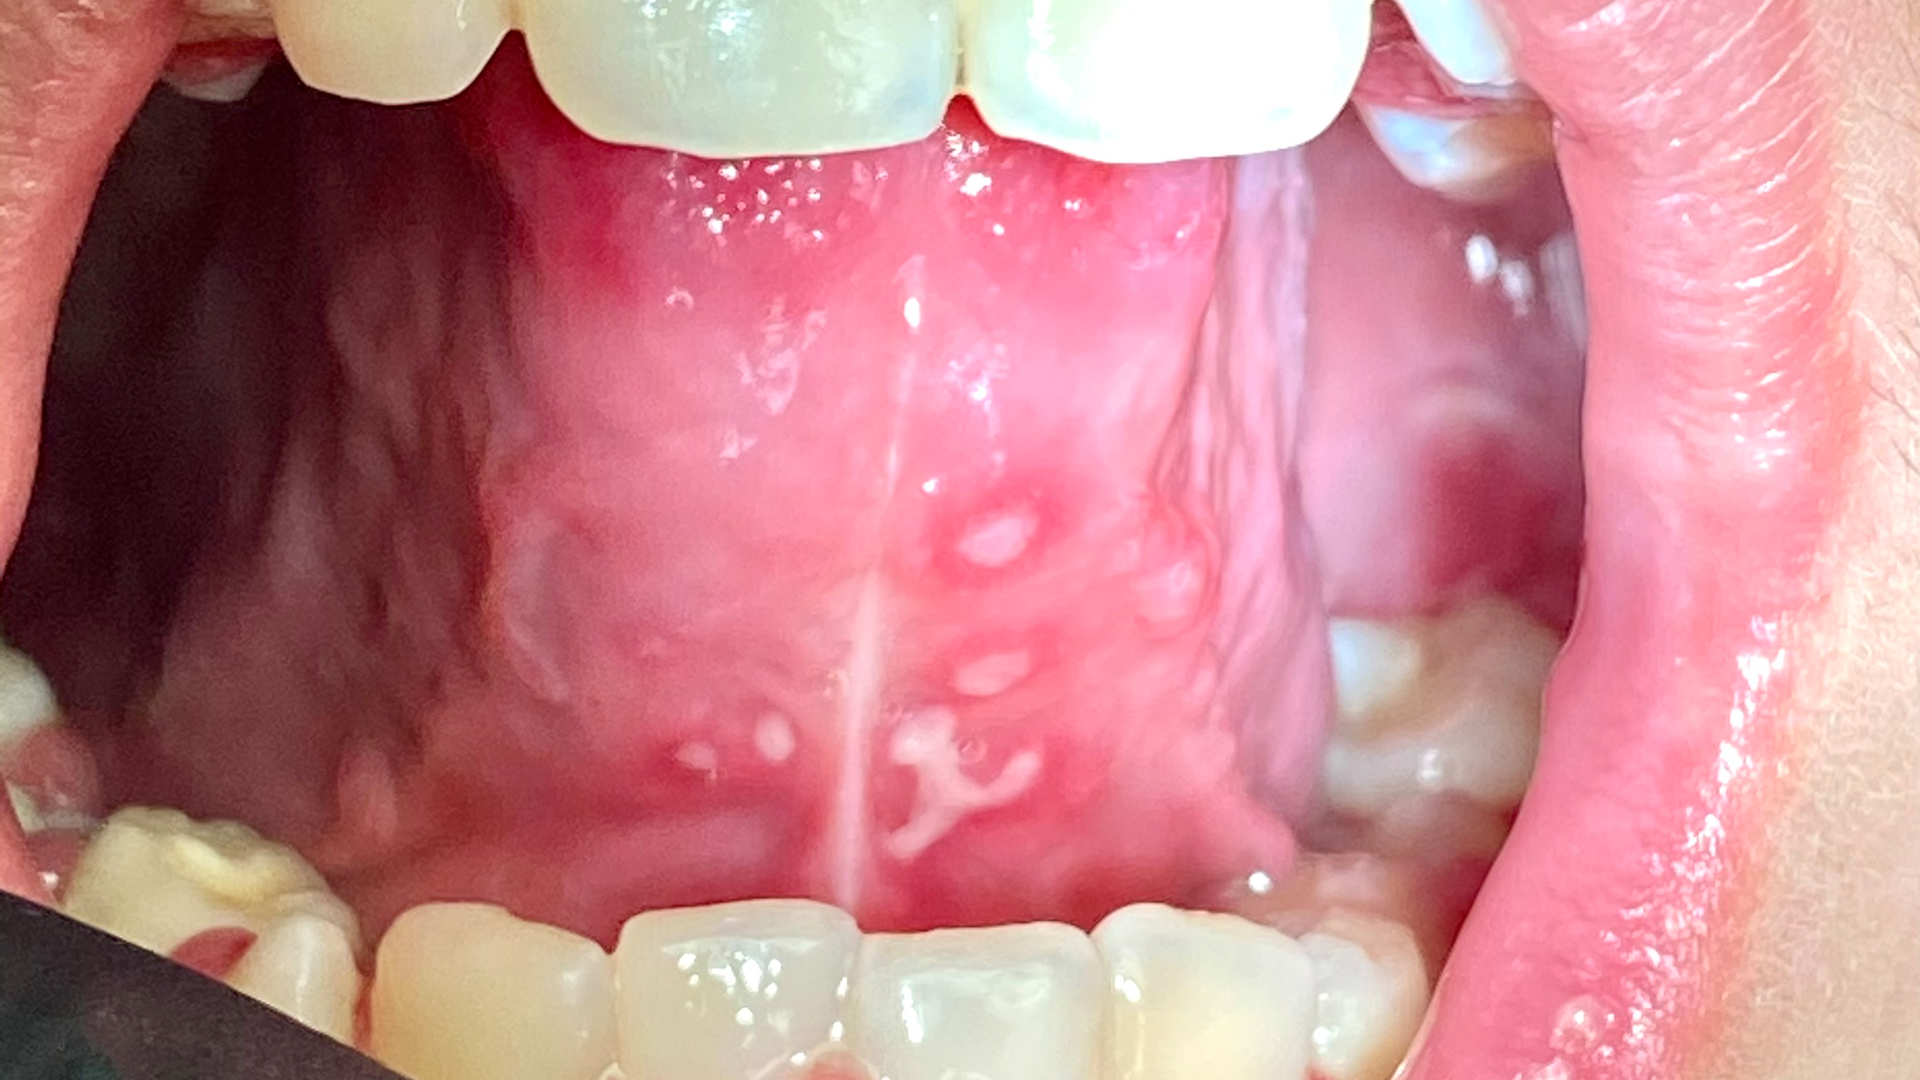

This 12-year-old presented with his mom for a dental visit. The chief complaint was that he was not feeling well, his mouth hurt, he couldn’t eat, it was painful to swallow, and he’d missed out on the last week of school. In general, his health history was unremarkable, temp was low-grade (99.8), and despite not being 100%, he was a trouper. Fist bumps, kiddo.

Note: The pictures are not of the highest quality as the patient was in extreme discomfort when I took them.

Definitive diagnosis is likely one of two: Herpangina or acute primary herpetic gingivostomatitis

The saying “nothing is for certain unless it’s in a petri dish” stands true in all pathology cases, including this one. However, based on the symptoms and clinical presentation, I was able to surmise that it was more than likely either herpangina or APHG, although I’m leaning toward APHG.